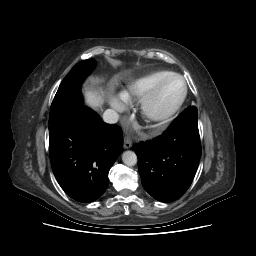

Generated VENOUS CT scan (A→B translation)

No window - Raw intensity values

Lung window (WL -600, WW 1500 β†’ Low βˆ’1350, High +150)

Mediastinum window (WL 40, WW 400 β†’ Low βˆ’160, High +240)